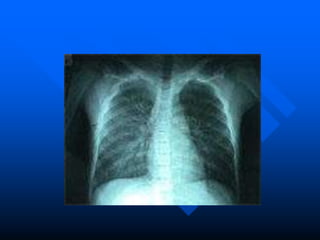

• El 90% de las muertes es por causa de

la Neumonía

• La Neumonía en Chile es la principal

causa de mortalidad infantil tardía